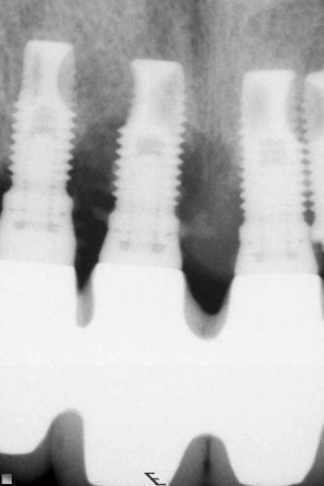

(1.) Peri-implantitis bone loss.

Figure 1

(2.) Peri-implantitis bone loss.

Figure 2

Peri-implantitis is defined as a bacterial plaque-associated pathological condition related to oral biofilm occurring in tissues around dental implants, characterized by inflammation in the peri-implant mucosa and subsequent progressive loss of surrounding bone1-8(Figure 1 and Figure 2). Food impaction is a contributing but not a primary factor in the disease process.